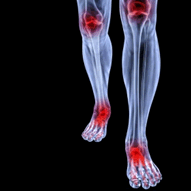

Arthritis is commonly used as a general term to describe a disease that causes inflammation and stiffness of small joints in the body. Included in the arthritis category are rheumatoid arthritis and osteoarthritis, which are also the “most common types of arthritis, affecting 1.5 million and 27 million Americans, respectively.” Rheumatoid arthritis can develop quickly, usually affecting the small joints, while osteoarthritis develops over time and can affect any joint on the body. Arthritis pain symptoms are sporadic and should be treated immediately.

Arthritis is commonly used as a general term to describe a disease that causes inflammation and stiffness of small joints in the body. Included in the arthritis category are rheumatoid arthritis and osteoarthritis, which are also the “most common types of arthritis, affecting 1.5 million and 27 million Americans, respectively.” Rheumatoid arthritis can develop quickly, usually affecting the small joints, while osteoarthritis develops over time and can affect any joint on the body. Arthritis pain symptoms are sporadic and should be treated immediately.

Arthritis is a joint disorder that involves inflammation of different joints in your body, such as in your feet. Arthritis is often caused by a degenerative joint disease and causes mild to severe pain in all affected areas. On top of this, swelling and stiffness in the affected joints can also be a common symptom of arthritis.

Rheumatoid arthritis is commonly known as an inflammatory autoimmune disease that leads to swelling in the joints in areas of the body like the hands and feet. Constantly managing your rheumatoid arthritis is vital to reducing the onset of symptoms and the progression of the disease. Rheumatoid arthritis is also suggested to be linked to a higher risk of heart disease, due to drastic changes in lifestyle.

Rheumatoid arthritis is commonly known as an inflammatory autoimmune disease that leads to swelling in the joints in areas of the body like the hands and feet. Constantly managing your rheumatoid arthritis is vital to reducing the onset of symptoms and the progression of the disease. Rheumatoid arthritis is also suggested to be linked to a higher risk of heart disease, due to drastic changes in lifestyle.

Rheumatoid Arthritis (RA) is an autoimmune disorder in which the body’s own immune system attacks the membranes surrounding the joints. Inflammation of the lining and eventually the destruction of the joint’s cartilage and bone occur, causing severe pain and immobility.

Although RA usually attacks multiple bones and joints throughout the entire body, almost 90 percent of cases result in pain in the foot area.

- Swelling & pain in the feet

- Stiffness in the feet

- Pain on the ball or sole of feet

- Joint shift and deformation